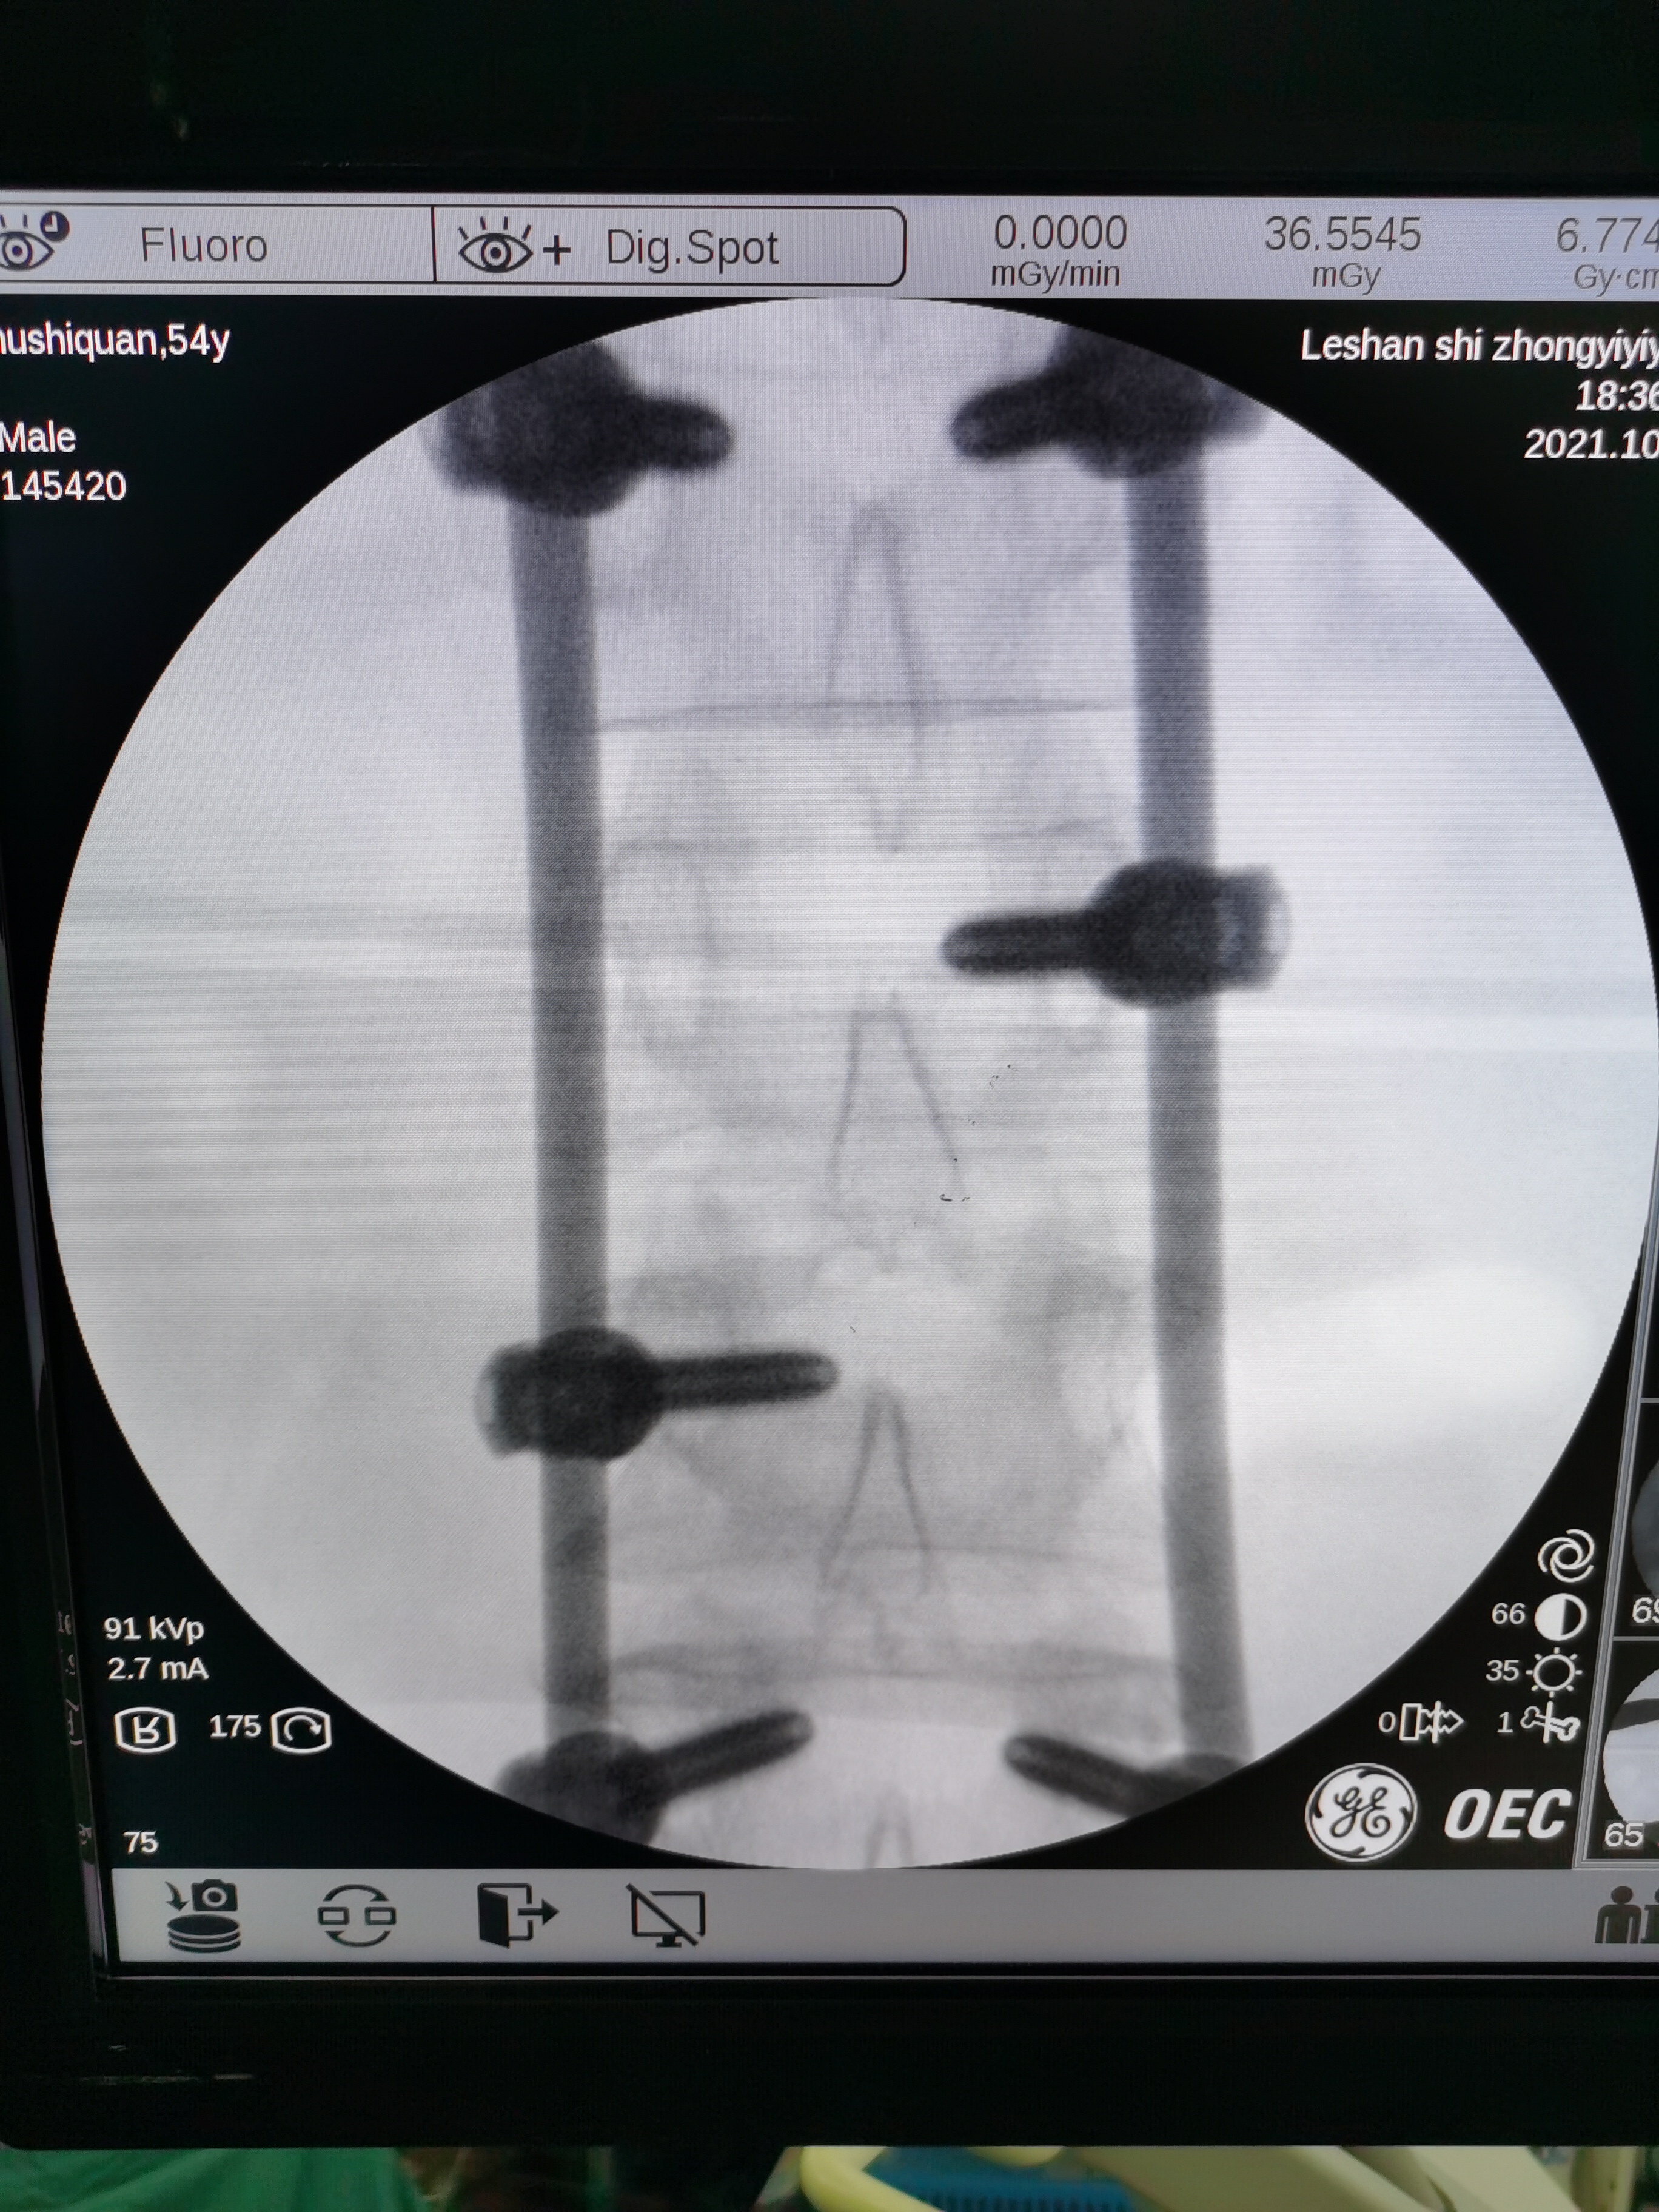

「该患者入院时,大小便等基本生活无法自理,几乎等同半身不遂。而患者又为家庭主要劳动力之一,生活无法自理使其十分焦虑和痛苦。」市中医医院骨伤科副主任高霖告诉记者,经过科室团队研究讨论后,拟定了两种可行方案,一种为开放性手术,一种利用科室新引进的 C 型臂透视机,行多节段微创手术。

「微创手术相对于传统的开放式手术来讲,具有伤口更小、出血量更少、恢复期更短且术后感染风险小等多项优势,对患者来说是最优选择。而对医生来说却是技术的考量。」高霖介绍到,若行开放式手术,患者伤口约为 20 cm 长,暴露性较强,术中可操作空间更大。而微创手术开口仅为 3 个 1 cm 的伤口,需要将 6 个螺钉和 2 个钉棒固定在患者骨折处,操作难度大,对医生技术要求非常高。「微创手术,我们科室开展过不少,而多节段的是首例。」

术中,6 个螺钉和 2 个钉棒不偏不倚地固定在胡先生骨折处,其脊柱的序列、高度得以恢复、脊柱的稳定性得以重建,手术花费 1 个半小时,出血量仅为 50 ml。